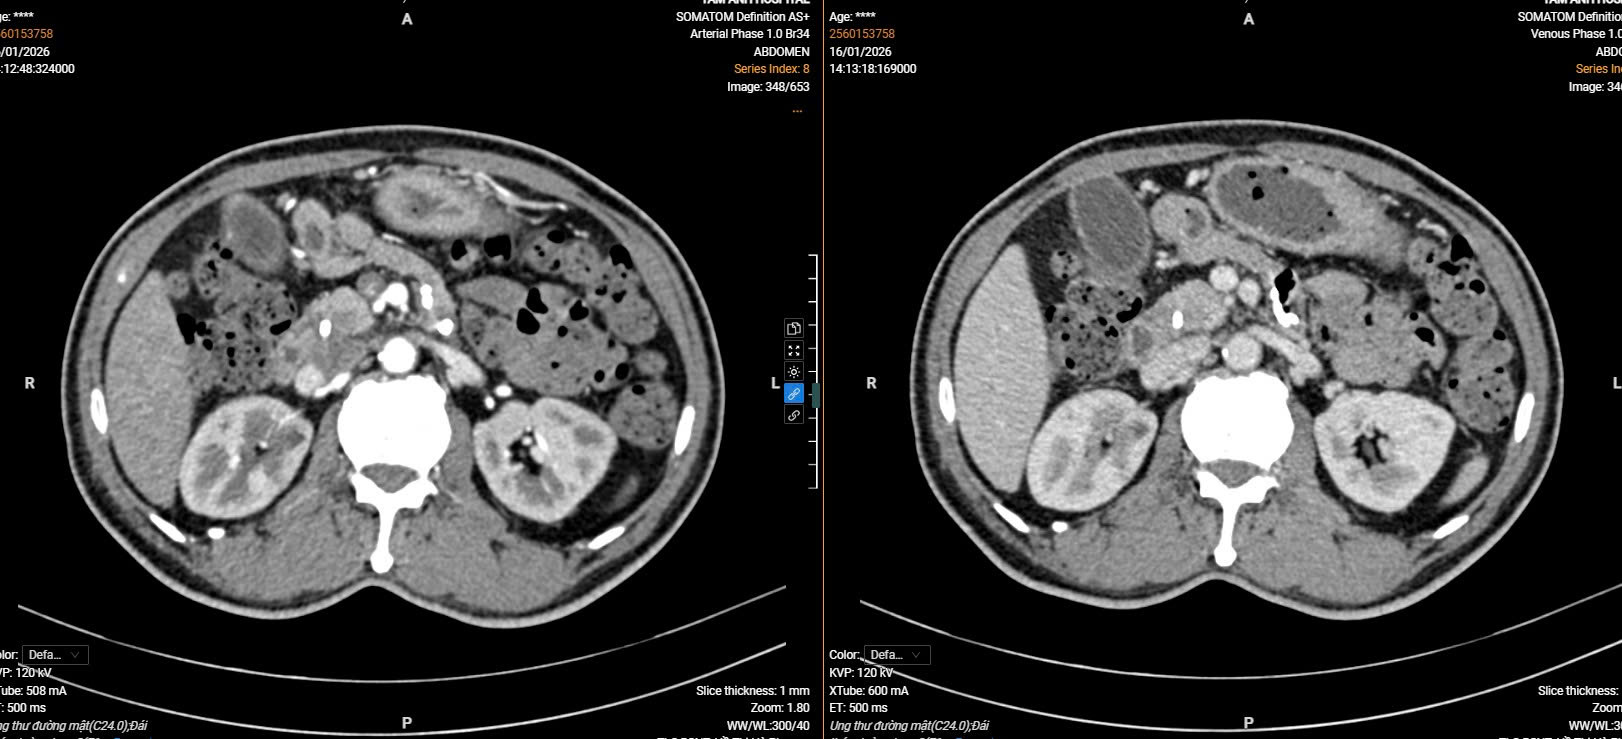

Ông Đ.V.L (64 tuổi) nhập viện với biểu hiện đau bụng âm ỉ kèm vàng da – những triệu chứng rất dễ nhầm lẫn với các bệnh lý tiêu hóa thông thường. Tuy nhiên, kết quả tầm soát chuyên sâu đã đưa ra một chẩn đoán chấn động: Bệnh nhân mắc đồng thời ung thư ống mật chủ (hệ tiêu hóa) và ung thư bàng quang (hệ tiết niệu

Theo các chuyên gia, tỷ lệ mắc cùng lúc ung thư ở hai hệ cơ quan khác nhau như thế này là cực kỳ hiếm gặp trong y văn (thông thường chỉ hay gặp ung thư ở hai vị trí khác nhau trên cùng hệ thống ống tiêu hóa). Việc phát hiện tình cờ khi đi kiểm tra sức khỏe đã mở ra "cánh cửa hẹp" đầy hy vọng cho bệnh nhân trước khi bệnh tiến triển sang giai đoạn muộn.